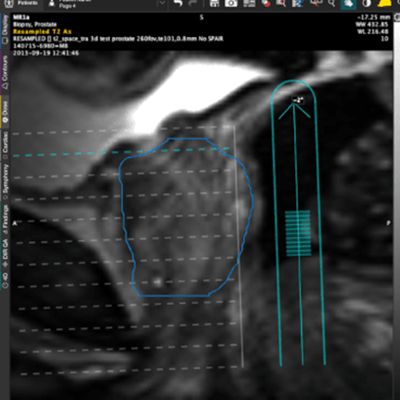

Brachytherapy Planning Using MR Fusion

MIM Symphony LDR allows for MR fusion and CT-based planning for prostate. It is a fully-featured solution without add-on modules.

Provides seamless MR-to-ultrasound registration.

Helps you to eliminate misalignments and deformation errors during ultrasound acquisition.

Rapid fusion of MR contours with automatic capture of transverse images.

Reorient the MR to match the patient orientation during the procedure.

Overlay the MR prostate volume onto the live ultrasound prior to the seed implant.